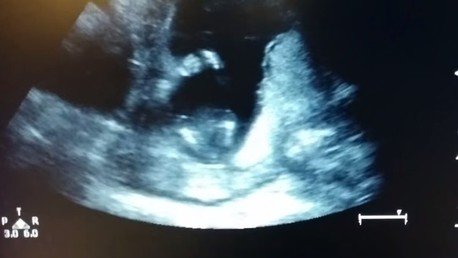

Un feto de 14 semanas aplaude durante una ecografía

Para sorpresa de todos una ecografía ha revelado el 'gran estilo' que tiene dando palmas este feto de 14 semanas. "Es una experiencia que jamás olvidaré. No hay misterio. Fue increíble", aseguró la futura mama, Jen Cardenal. Según los médicos, los fetos hacen todo tipo de movimientos sin sentido en el útero.